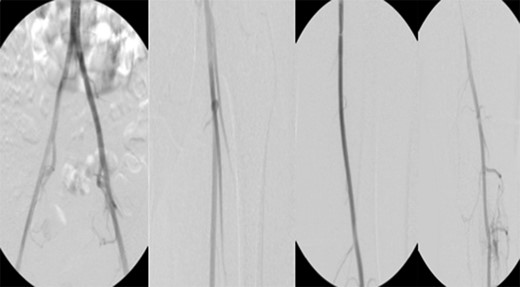

Patient underwent a left lower extremity angiogram. During the procedure she was found to have patent aorta and bilateral common iliac artery. There was no disease visualized in the left external iliac artery, common femoral artery (CFA), SFA, patent previously placed stent, patent above and below the knee PA and two vessel run off to the foot (Fig. 1). Upon delayed fluoroscopic images we identified contrast filling the deep venous system rather quickly suggesting a high volume fistula (Fig. 2). We then identified the fistula between ATA and ATV. Although ATA was previously ligated there was retrograde filling of the artery from unnamed branches, which communicated with the venous system as shown in. In the midcalf (ATA) was cannulated with a micropuncture needle. Micropuncture wire was inserted and a 5-Fr sheath was inserted after exchanging over wire. At this point VortX coils (Boston Scientific) were placed from the curve of ATA until the whole AVF was sealed. Anterograde angiogram showed no flow through the fistula (Figs 3 and 4). There was a palpable PT and DP pulse at the completion of the procedure. Sheath was removed, pressure dressing applied. Patient was discharged home same day. Recovery has been unremarkable. Three months follow-up claudication symptoms have significantly improved.

VortX coils (Boston Scientific) were placed from the curve of anterior tibial artery to its communication with venous system.